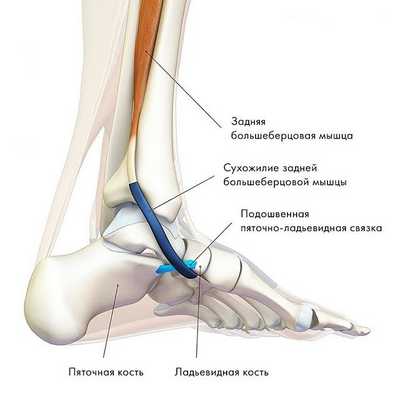

Дисфункция сухожилия задней большеберцовой мышцы

Этот синдром является причиной патологии медиальной части заднего отдела стопы, часто просмотренной и неправильно диагностированной, особенно на ранних стадиях. Это является прямым результатом потери функции сухожилия задней большеберцовой мышцы.

Хроническое воспаление ведет к дегенерации и растяжению сухожилия с формированием интерстициального отека, истончением и хроническим повреждением сухожилия. При отсутствии лечения все это ведет к нарушению выравнивания заднего и среднего отделов стопы с пронацией пятки, плантафлексии тарана, подвывиху в таранно-ладьевидном суставе и как результат формирование односторонней плоской стопы.

Задняя большеберцовая мышца активна в течение фазы опоры, включается сразу после контакта пятки с опорой и быстро прекращает сокращаться после поднятия пятки. Ее брюшко начинается глубоко внутри задней части нижней конечности, сухожилие следует вниз до задней части медиальной лодыжки, где находится кпереди от сухожилия длинного сгибателя пальцев, заднего большеберцового нейрососудистого пучка (задняя б/б артерия, вена и нерв) и сухожилия сгибателя большого пальца. Все эти структуры ограничиваются удерживателем сгибателей возле медиальной лодыжки. Сухожилие задней б/б мышцы проходит в борозде позади и ниже медиальной лодыжки, разделяясь на 3 части у медиальной стороны тарана. Передняя часть прикрепляется к бугристости ладьевидной кости, средняя часть продолжается в плантарную тарзальную область и прикрепляется к плантарной части клиновидных костей, кубовидной и в основании 2, 3 и 4 метатарзальных костей. Задняя часть внедряется как пучок в переднюю часть нижней пяточно-ладьевидной связки. Медиальная лодыжка работает как многороликовый блок, позволяя сухожилию задней б/б мышцы изменять направление тяги, и эти точки прикрепления обеспечивают супинацию заднего и среднего отделов стопы во время переноса веса, в то время как происходит стабилизация арочной конструкции среднего отдела.

Главная функция задней б/б мышцы - добиться супинации в подтаранном суставе и приведения переднего отдела стопы вокруг косой оси среднеплюсневого сустава.

МРТ наиболее полезный метод исследования сухожилий вокруг голеностопного сустава и выявления повреждений. Другие диагностические тесты включают сканирование костей и введение радиоконтрастного вещества в сухожильное влагалище.